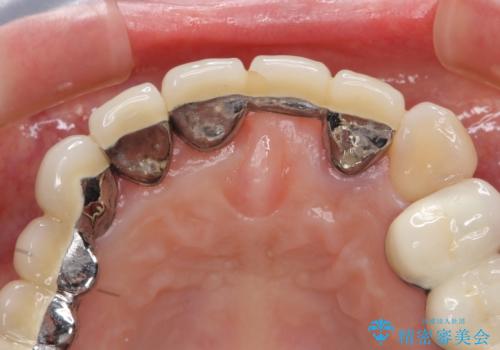

前歯ブリッジのやりかえ

- 前歯の審美障害、見た目の改善を希望され来院されました。

歯肉縁下カリエスも認められるため、挺出を行いセラミックブリッジを審美的に新製します。

- 47万円(仮歯×3・ファイバーコア×2・ジルコニアクラウン×3 歯の挺出)費用は治療当時の料金となります